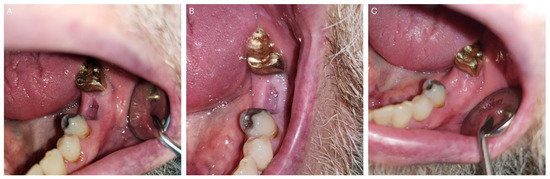

| 1 | M | 69 | Squamous cell carcinoma | Base of Tongue (Oropharynx) | 70 Gy/(Yes) | Mandibular First Molar (#19) | High | Complete Healing |

| 2 | M | 70 | Squamous cell carcinoma | Ventral Tongue/Floor of Mouth (Oral Cavity) [Right] | 70 Gy/(Yes) | Mandibular Incisors and First Molar (#24, #25, #26, and #30) | High | Complete Healing |

| 3 | F | 59 | Squamous cell carcinoma | Tonsil (Oropharynx) [Right] | 70 Gy/(Yes) | Mandibular First Molar (#19) | Moderate | Complete Healing |

| 4 | M | 75 | Adenoid cystic carcinoma | Hard palate/Maxillary Sinus (Oral Cavity) [Left] | 66 Gy/(No) | Mandibular Second Molars (#18 and #31) | Moderate | Complete Healing |